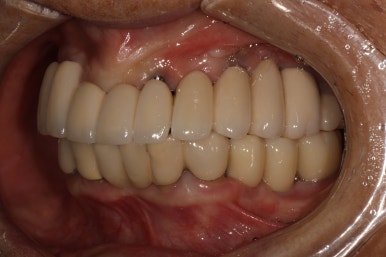

어금니 우측

좌우측 측면 사진 비교시, 아래 어금니 임플란트로 깔끔하게 메꿔진 빈 공간이 인상적입니다!